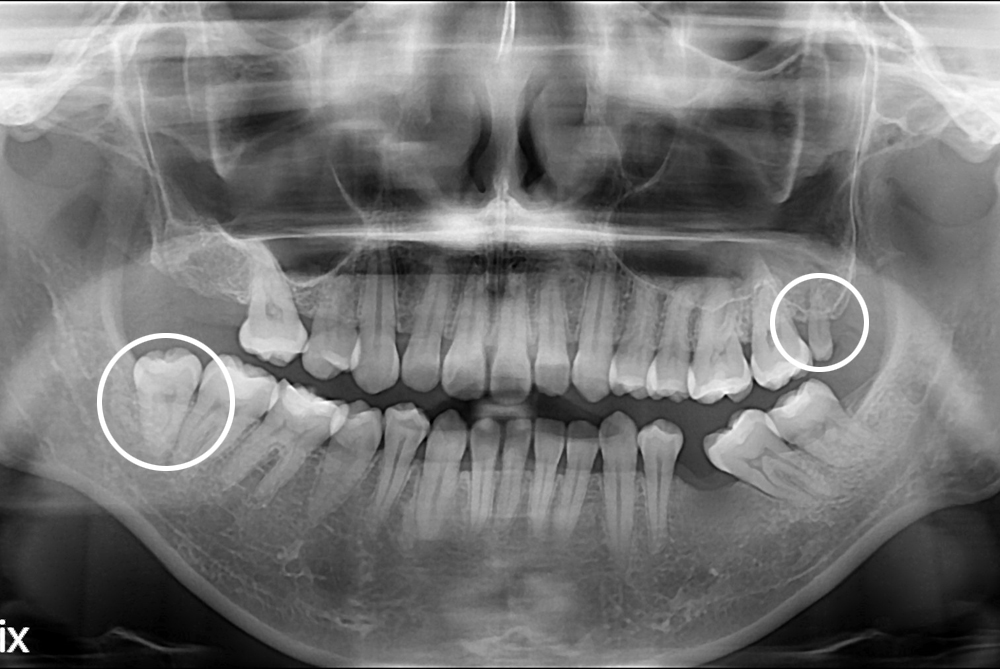

[사랑니] 난발치 사랑니 발치

치료전 : 2017-09-14